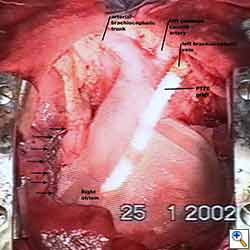

Pericardial reconstruction after anterior mediastinal tumor resection

Some pericardial defects resulting after partial pericardiectomy for invasive anterior mediastinal masses need pericardial reconstruction (Figures 4a-c). This is not the case for small pericardial defects, but large and lateral defects require reconstruction, especially if a lung resection has been performed. In the case of pericardiectomy with pneumonectomy, the postpneumonectomy space plays an important role in the pathogenesis of cardiac herniation. En bloc resection of a mediastinal tumor, the pericardium and the lung increases the risk of herniation in a similar fashion. In the absence of a lung resection, lung atelectasis can also increase this risk. Following complex resections requiring vascular resection followed by reconstruction, the reconstruction can stabilise the vascular prosthesis and prevent it from kinking (Figure 4c). Another potential advantage of pericardial reconstruction is that in the event of a re-do sternotomy, the risk of cardiac laceration is reduced because it prevents sternal-cardiac adhesions from forming [5]

Video 1 depicts a pericardial reconstruction with Marlex after a right completion pneumonectomy with pericardiectomy for lung adenocarcinoma (see also Figure 1). The technique of pericardial reconstruction after the resection of invasive mediastinal tumours is illustrated in Figures 8a-c). Video 2 depicts a pericardial reconstruction with Mersilene mesh after the resection of a malignant thymoma invading the anterior pericardium (see also Figure 4b). The technique of right pericardial reconstruction after extrapleural pneumonectomy is illustrated in Figures 9a and 9b). Video 3 depicts a pericardial reconstruction using Gore-Tex Dual Mesh after a left extrapleural pneumonectomy (see also Figure 3). Care must be taken to prevent constriction (Figure 10).